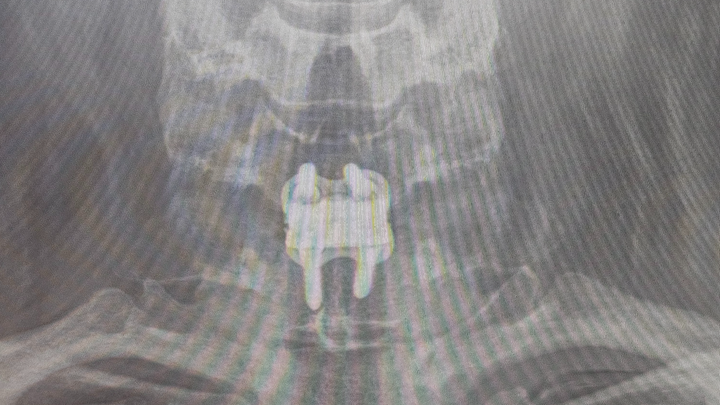

For those who may not know: In 2023 I was in a car accident that caused my disc between c6 and c7 yo herniate 5mm, pinching a nerve. I finally was able to get surgery to fix this in January of this year, but I've been out of work longer than expected and ran out of PTO. Unfortunately I don't exactly have parental support to cushion me in this time (RIP) my community has been saving me through this ❤️